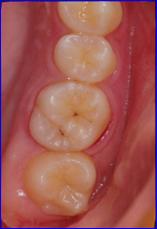

A:  奥歯の噛み合わせには、山あり谷ありとても複雑な形をしていて、その谷底はとても細い隙間になっています。

細くて深い隙間ですから歯ブラシの毛先が届とどきません。隙間は汚れで埋まっていて、どんなにきれいにブラッシングしても取り除けません。

ですから、むし歯にとてもなりやすいのです。

さらに生えて間もない歯は表面のエナメル質が未成熟で、むし歯菌が作り出す酸に対する抵抗力が弱いので、むし歯にたいへんかかりやすいのです。

シーラントというのは、あらかじめ、この溝を合成樹脂で埋めてしまう予防処置です。

シーラントは歯に接着するレジンという材料を用いて行うことが多く、きちんと歯質に接着させるためには、薬剤によって歯面を処理後、十分乾燥した状態で溝を覆うように塗布する必要があります。

当院ではラバーダムという方法を用いて防湿を行ってシーラントを行っています。

きちんとシールされていればとても有効なむし歯の予防方法です。

治療前 シーラント後